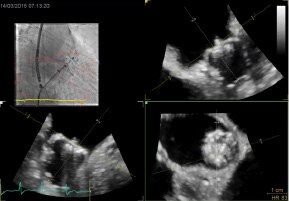

- INTERACT ViewX è un kit di connessione per visualizzare le immagini interventistiche sul display del sistema ecografico GE. Richiede i sistemi Vivid E95 o Vivid S70N venduti separatamente. Si riferisce alle funzioni di Innova IGS 5, Innova IGS 6, Discovery IGS 7 e Discovery IGS 7 OR

- I sistemi Vivid sono venduti separatamente

- Cvi42 Mitral, distribuito da GE per Circle Cardiovascular, è un'applicazione leader che offre un set di strumenti e un flusso di lavoro completi per la valutazione della valvola mitrale. Accessibile solo su AW 4,7. Cvi mitral è venduto separatamente. Potrebbe non essere disponibile in tutti i mercati. Contattate il rappresentante commerciale locale